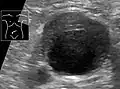

Aortic measurement on abdominal ultrasonography in the axial plane between the outer margins of the aortic wall[39]

Ultrasonography in the sagittal plane, showing axial plane measure (dashed red line), as well as maximal diameter (dotted yellow line), which is preferred